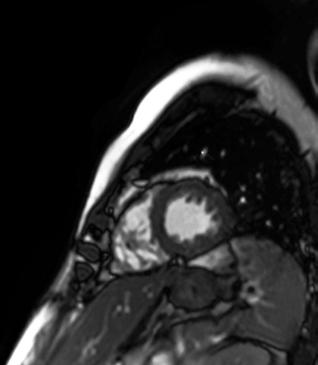

Cardiac screening for proactive health surveillance is firmly on the radar for all sporting organisations. This is not only to identify undetected anomalies that could put life and health at risk, but also to monitor for the onset of coronary artery disease as players age. Indeed, from youth teams to the veteran professional footballer, anyone undertaking vigorous training and competitive matches is regulated to receive cardiology profiling every 2 years1

The imaging tool that has traditionally been used is ultrasound echocardiography, looking at the structure of the heart at rest and during stress exercise. Now, and increasingly, the structure and functionality of the heart is examined via the latest generation in MRI.

For example, new developments have accelerated the examination time for cardiac MRI, with fewer patient breath holds needed to deliver much more detailed, richer image outputs that give another level of screening and profiling of the more subtle presentations of cardiac anatomy.